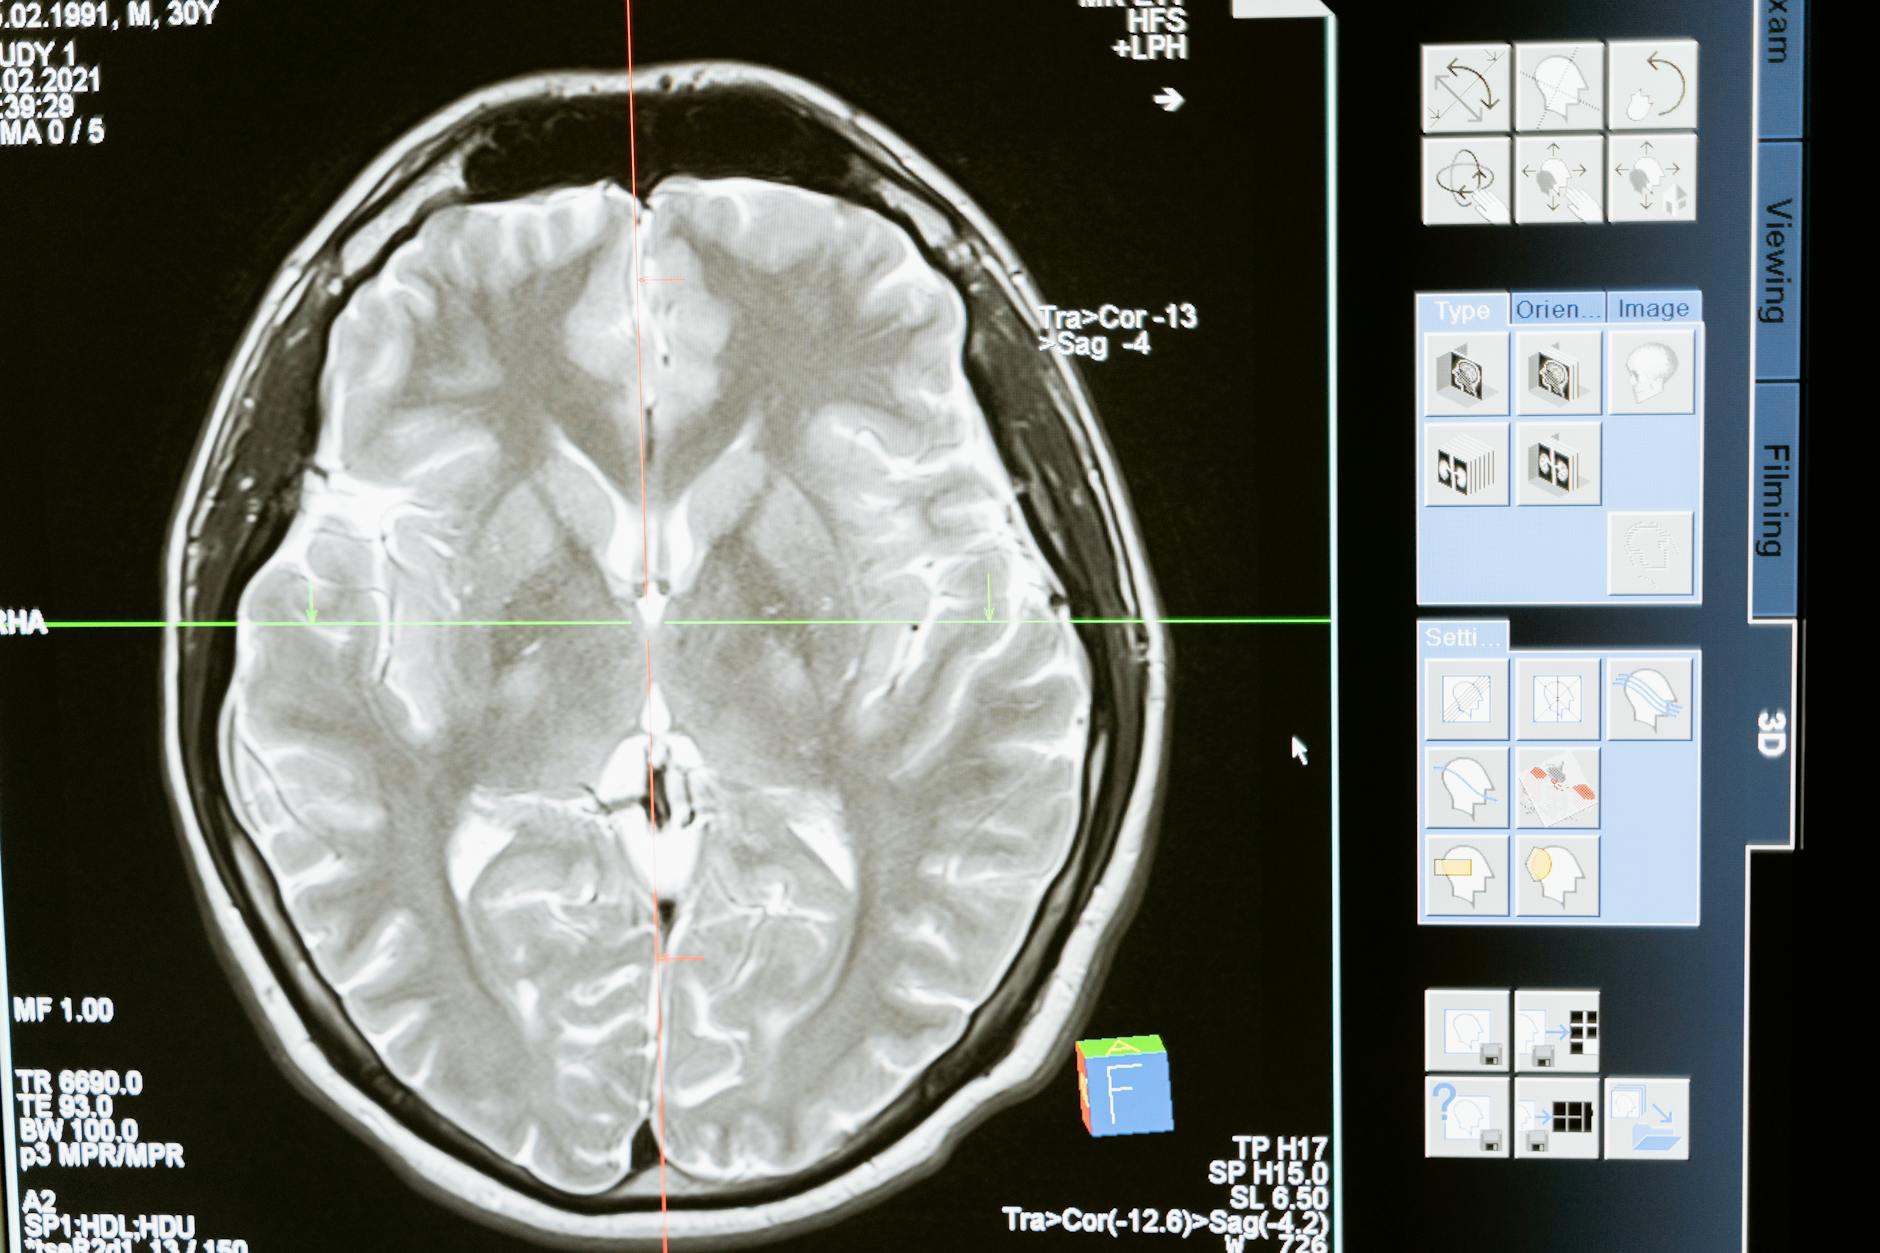

専門家の間では、単一のツールだけで判断を下すのではなく、複数の観察・検査を組み合わせるアプローチが推奨されています。検査の点数だけでなく、産業医や保健師による問診や日常業務のパフォーマンス観察を加えることで、より信頼性の高いアセスメントが可能になります。なお、脳MRIや血液バイオマーカー検査は医療機関との連携が前提となるため、産業保健のスクリーニングとしては補助的な位置づけになります。